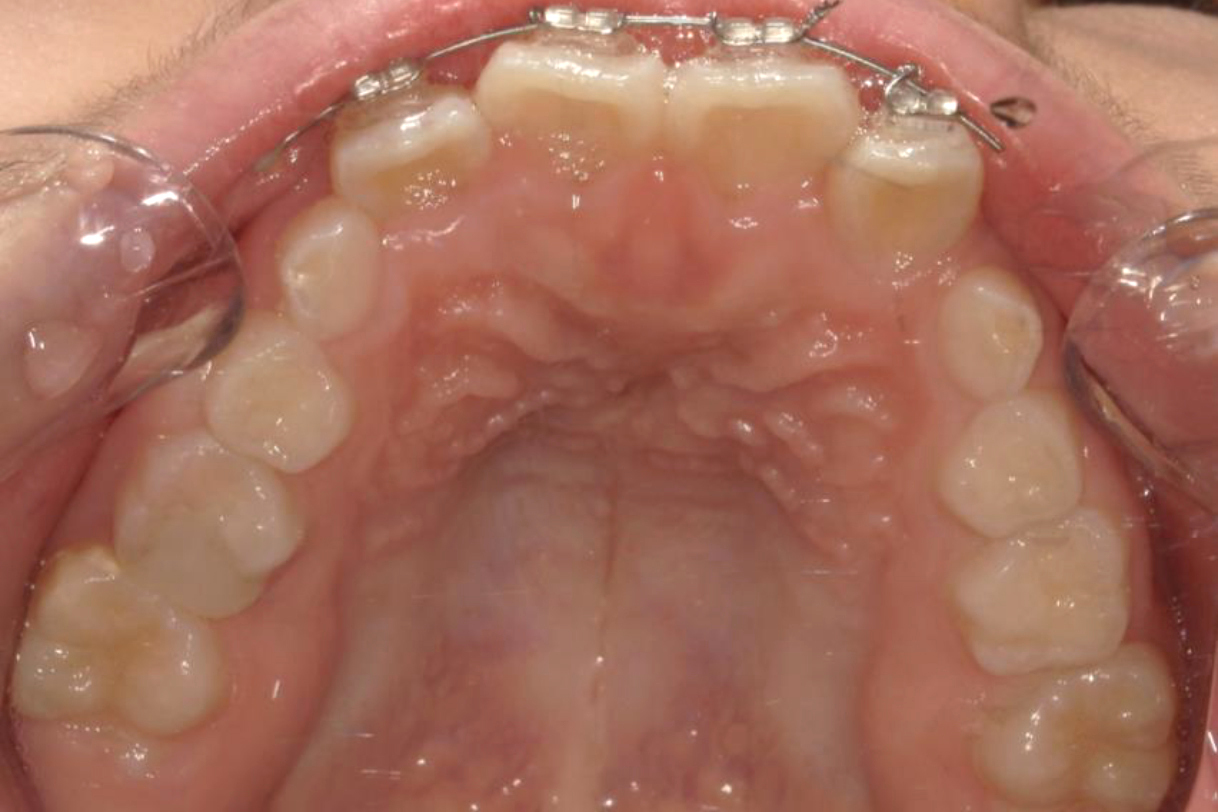

2022年11月

浜松市中区の症例紹介 マウスピース矯正

2024年4月

初診時年齢:50代女性

治療:前歯部矯正

治療法:マウスピース型矯正装置(インビザライン)

治療期間:1年6ヶ月

費用:792,000円(税込)

リスク・副作用:装置装着による違和感、歯の移動時の痛み